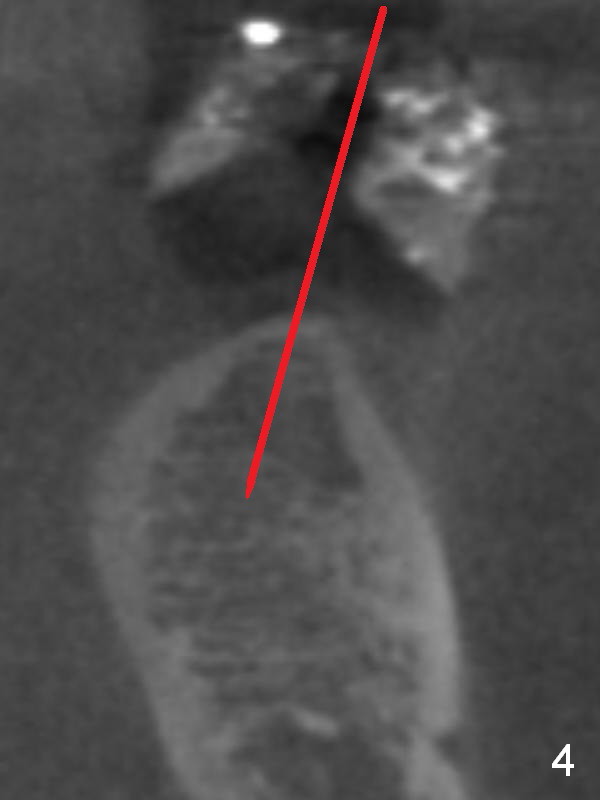

CBCT 3-D image taken with scan stents at the sites of #18 and 19 shows 2 Mental Foramina (Fig.1 *) in the left mandible.  Both sagittal (Fig.2) and coronal (Fig.3) sections show low density at the crest of #19 of a 55-year-old man (arrowheads).  The crest is also narrow.  After making an initial osteotomy through the stent (Fig.4 red arrow), remove the latter (Fig.5).  Ridge split is initiated with wheel saws (Fig.6 blue line).  The osteotomy is enlarged with bone expanders (Fig.7 green circle) with ridge split (blue lines).  Finally an implant is placed (Fig.8 pink circle) with placement of bone graft in the space of the ridge split (yellow circles).